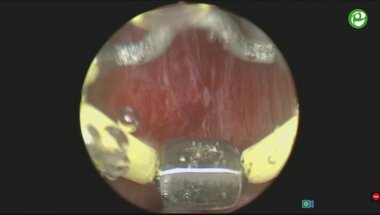

Биполярная электроэнуклеация гиперплазии простаты

Сорокин Н.И. - Основы трансуретральной энуклеации простаты